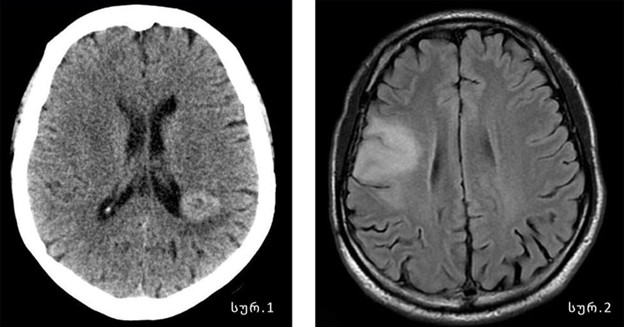

თუ შეგიძლიათ, რომ გაგვიზიაროთ, როგორ ხდება თავის ტვინის სიმსივნის დიაგნოზის დასმა?ტვინის სიმსივნის განვითარებისას, დროული/ადრეული დიაგნოზი ხშირ შემთხვევაში საგრძნობლად ეხმარება მკურნალობის პროცესს და წარმატებულ გამოსავალს. ტვინის სიმსივნის დიაგნოზირება, როგორც წესი, ხდება კომპიუტერული (სურ. 1) ან მაგნიტურ რეზონანსული (სურ. 2) ტომოგრაფიის (მრტ) გამოყენებით. ასევე ექიმმა შეიძლება ჩაატაროს დამატებითი გამოკვლევები/ტესტები, რომ გამორიცხოს ან დაადასტუროს ესა თუ ის დიაგნოზი.